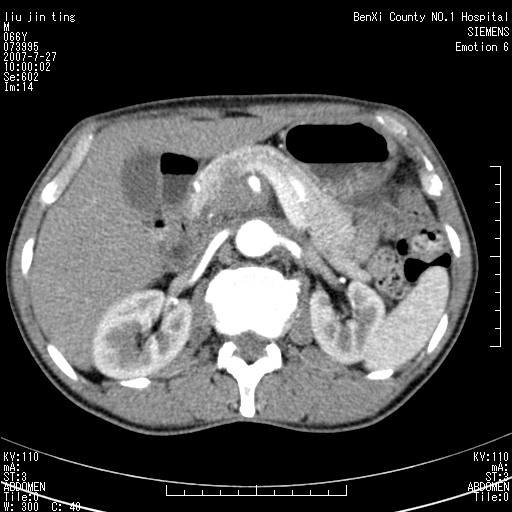

腹痛,背痛,无恶心呕吐,不黄,彩超示胰腺钩癌,ct扫描病灶平扫30-40hu,增强后动脉期40--60hu,静脉期50-68hu,真的是钩突上的么?您要试一试么?

动脉期

沿着肠系膜上动脉呈匍匐性生长的软组织肿块,形态不规则,包绕肠系膜上动脉,呈明显强化,考虑来源于肠系膜的恶性肿瘤

肠系膜根部肿块,累及肠系膜上动脉,考虑肿大淋巴结累及肠系膜上动脉.

腹腔干至肠系膜上动脉水平肿大淋巴结影可能性大.

沿着肠系膜上动脉呈匍匐性生长的软组织肿块,形态不规则,包绕肠系膜上动脉,呈轻-中度强化,考虑来源于肠系膜的恶性肿瘤。

钩突是正常的,只见腹膜后淋巴结的肿大,考虑淋巴瘤或转移可能。

支持!恶性纤维组织细胞瘤可能,与淋巴瘤及淋巴结转移鉴别(腹主动脉周围清晰,其他部位亦未见明显肿大淋巴结)。